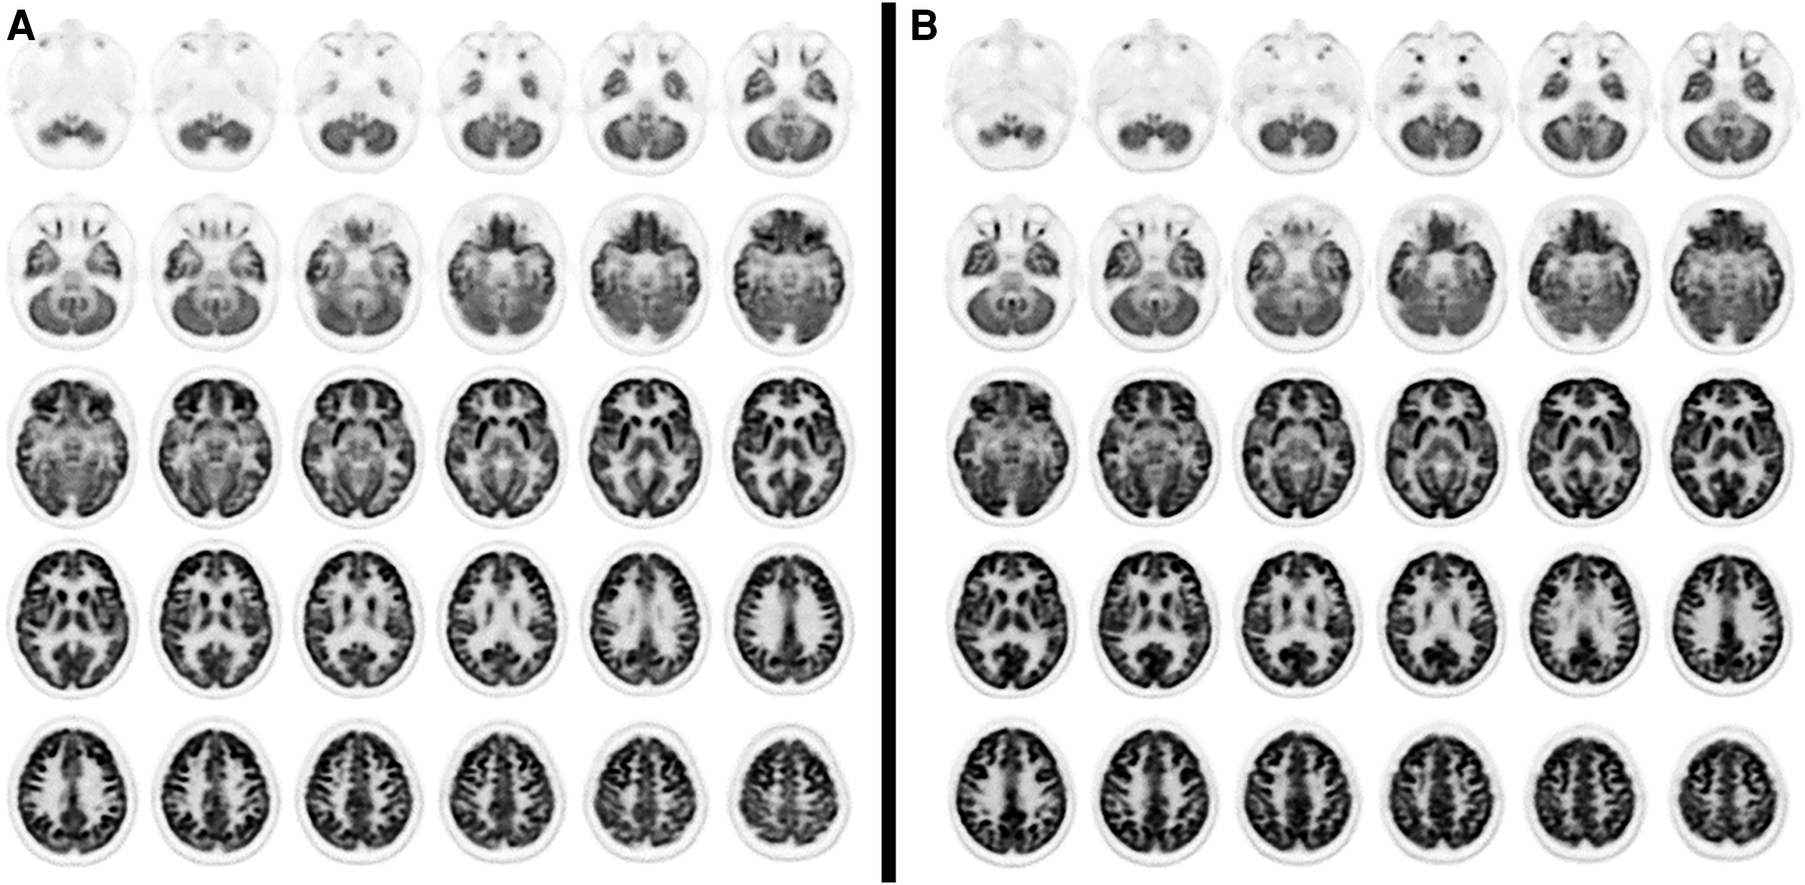

Visual analysis of PET images showed a moderate reduction in 18F-FDG uptake in the bilateral mesial-temporal region (Figure 1); these findings were confirmed by the voxel-wise analysis. The SPM8 analysis showed, at a height threshold of p < 0.001 (uncorrected), a significant hypometabolism (p < 0.001) in both patients (n = 2), as compared to healthy subjects (n = 19), in the left and right mesial-temporal regions with a peak in the bilateral hippocampus (right: MNI coordinates 22/-12/-20 mm with a T-score of 6.7; left: MNI coordinates −20/−16/−19 mm with a T-score of 6.1; Figure 2).

Figure 1. Axial PET slices showing areas of moderate glucose hypometabolism in bilateral mesial brain regions in case 1 (A) and case 2 (B).

Figure 2. Coronal and axial slices showing SPM areas of reduced brain metabolism superimposed on a T1 axial magnetic resonance reference atlas. The colored areas indicate the locations where the voxel values of both patients are significantly hypometabolic compared to healthy subjects (P < 0.001). The t-values are represented by the brightness of the color.